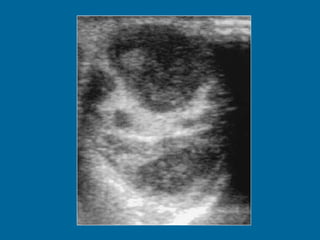

Image 1 (Ultrasound): Swelling of the right epididymis with associated mild right orchitis. Doppler images (not shown here) demonstrated increased vascularity.

Image 1 (Ultrasound):Swelling of the right epididymis with associated mild right orchitis. Doppler images (not shown here) demonstrated increased vascularity.